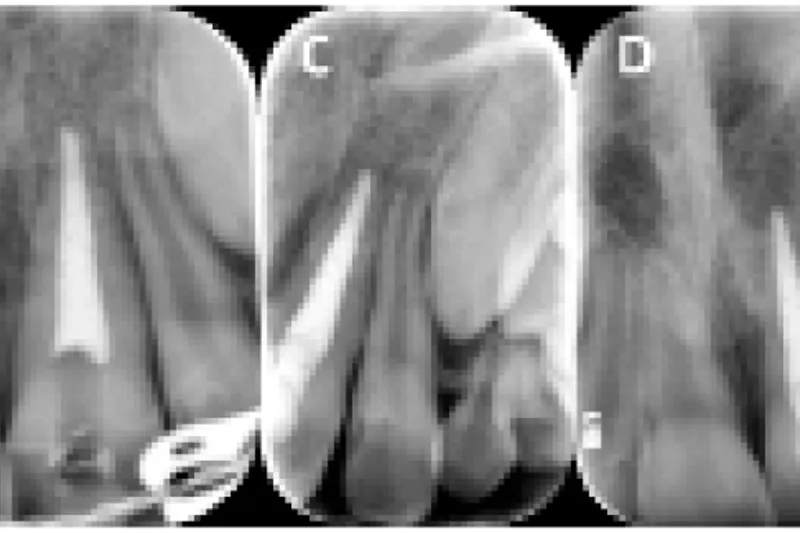

Rodresorptioner er en vigtig og alvorlig senfølge efter tandskader, især alvorlige luksationsskader. I artiklen præsenteres en klassifikation af eksterne rodresorptioner efter tandskader. De vigtigste kendetegn og kliniske manifestationer illustreres med patienteksempler. Det er særlig vigtigt at skelne de forskellige typer af resorptioner fra hinanden, da de skal behandles forskelligt. Infektionsrelaterede resorptioner kræver tidlig diagnostik og intervention, mens reparationsrelaterede resorptioner blot observeres. Erstatningsresorptioner med stigende infraokklusion må ikke observeres så længe, at kæbevæksten og alveolarprocessen påvirkes.

Risikoen for rodresorption efter tandskader er stor. Det er vigtigt at kende de forskellige varianter af rodresorption som følge af tandskader, eftersom de kræver forskellig indsats fra behandleren. Reparationsrelaterede rodresorptioner skal kun observeres, mens det ved infektionsrelaterede rodresorptioner er vigtigt med tidlig diagnostik og intervention for at stoppe infektionen og dens stimuli for videre udvikling af processen. Erstatningsresorption med stigende infraokklusion må ikke observeres for længe hos unge i vækst.

Root resorptions is a frequent consequence after traumatic dental injuries, in particular severe luxation injuries. This article presents classification of external root resorptions due to traumatic dental injuries. The main features and clinical picture are illustrated with clinical examples. It is important to distinguish the different types of root resorptions and their stimuli, as they should be treated different. Infection related resorptions demand early diagnoses and interventions, while repair related resorptions need observation only. Replacement resorptions with increasing infraocclusion should not be observed if maxillo- facial growth and alveolar process is affected.